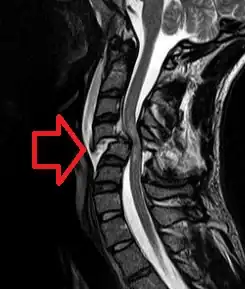

Нейрогенный шок — состояние организма человека, развивающееся вследствие повреждения спинного мозга, во время чего нарушается проведение импульсов симпатической нервной системы, а ничем не ограниченный тонус блуждающего нерва (лат. n.vagus) начинает доминировать. Ведущими клиническими признаками нейрогенного шока при повреждении спинного мозга являются артериальная гипотензия и брадикардия. По частоте повреждений отделов спинного мозга лидирует шейный, далее уровень грудопоясничного перехода позвоночника, реже грудной отдел и ещё реже уровень поясничного отдела позвоночника (повреждение конского хвоста). Нейрогенный шок должен быть дифференцирован от спинального шока, определяемого как арефлексию ниже уровня повреждения спинного мозга.

Клиническая картина нейрогенного шока и тяжесть состояния пациентов во многом зависит от уровня повреждения спинного мозга. Повреждения, локализованные выше первого грудного сегмента спинного мозга (Th1), приводят к разрушению проводящих путей спинного мозга, контролирующих деятельность всей симпатической нервной системы (регулирующей нормальное функционирование множества систем органов, в том числе жизненно важные – сердечно-сосудистая, дыхательная и другие).

Повреждения, локализованные в сегментах спинного мозга начиная с первого грудного и ниже, лишь частично нарушают деятельность симпатической нервной системы. Тяжесть проявлений нейрогенного шока уменьшается вместе со снижением локализации патологии спинного мозга. Так, например, повреждения верхних грудных сегментов сопровождаются более тяжелой клинической картиной чем, к примеру, повреждение конуса спинного мозга (на уровне грудопоясничного перехода позвоночника).